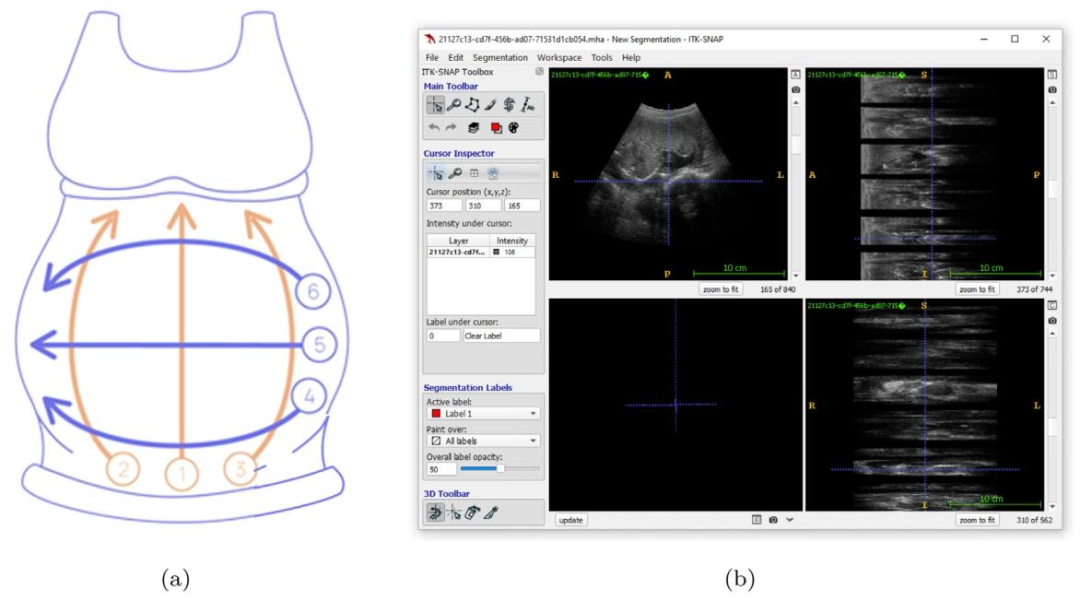

This work integrates rule-based modeling and visualizations withstatistical feature engineering and DL-based feature extraction to produce human-understandable explanations. This method bridges thegap between interpretable techniques’ transparency and black-box DLmodels’ predictive power. Fig. 1 shows an overview of the proposedmethod. First, some existing techniques are used in preprocessing, likedata augmentations, image resizing, and region of interest cropping.The resultant dataset is then fed into the custom MobileNetv2 DL modelfor feature extraction to capture complex visual patterns and get morediscriminative and informative deep features, which are crucial foraccurate classification. These extracted features are then used for statistical transformation to compute interpretable, summary-level insights.Next, a novel ZFMIS technique ranks and filters features based on theirinterpretive value. The filtered and selected features are then used totrain the decision tree and RuleFit interpretable rule-based models. Finally, Grad-CAM-inspired heatmaps (SFMOV) are generated to visualizethe most important statistical features and highlight spatial regions ofthe images that contribute significantly to the model’s decision-makingprocess. Visual overlays enhance statistical interpretation by illustrating how specific patterns affect categorization judgments, providingstakeholders with an intuitive understanding of the prediction model’sbehavior, a model-agnostic visual explanation technique.The pseudocode of the proposed methodology is presented in Algorithm 1. Each step is discussed in detail in the subsequent sections

本研究将基于规则的建模、可视化技术与统计特征工程及基于深度学习(DL)的特征提取相结合,生成人类可理解的解释。该方法填补了可解释技术的透明度与黑箱深度学习模型的预测能力之间的差距。图1展示了所提方法的整体框架:首先,采用一些现有技术进行预处理,如数据增强、图像 resize 和感兴趣区域裁剪;然后,将处理后的数据集输入定制的 MobileNetv2 深度学习模型进行特征提取,以捕捉复杂的视觉模式,获得更具判别性和信息量的深度特征——这些特征对准确分类至关重要;接着,利用这些提取的特征进行统计转换,计算可解释的、汇总级别的洞察;之后,一种新颖的 ZFMIS 技术根据特征的解释价值对其进行排序和筛选;再将经过筛选和选择的特征用于训练决策树和 RuleFit 这两种可解释的基于规则的模型;最后,生成受 Grad-CAM 启发的热图(SFMOV),以可视化最重要的统计特征,并突出对模型决策过程有显著影响的图像空间区域。视觉叠加通过说明特定模式如何影响分类判断,增强了统计解释的效果,为相关人员提供了对预测模型行为的直观理解,这是一种与模型无关的视觉解释技术。 所提方法的伪代码如算法1所示。后续章节将详细讨论每个步骤。